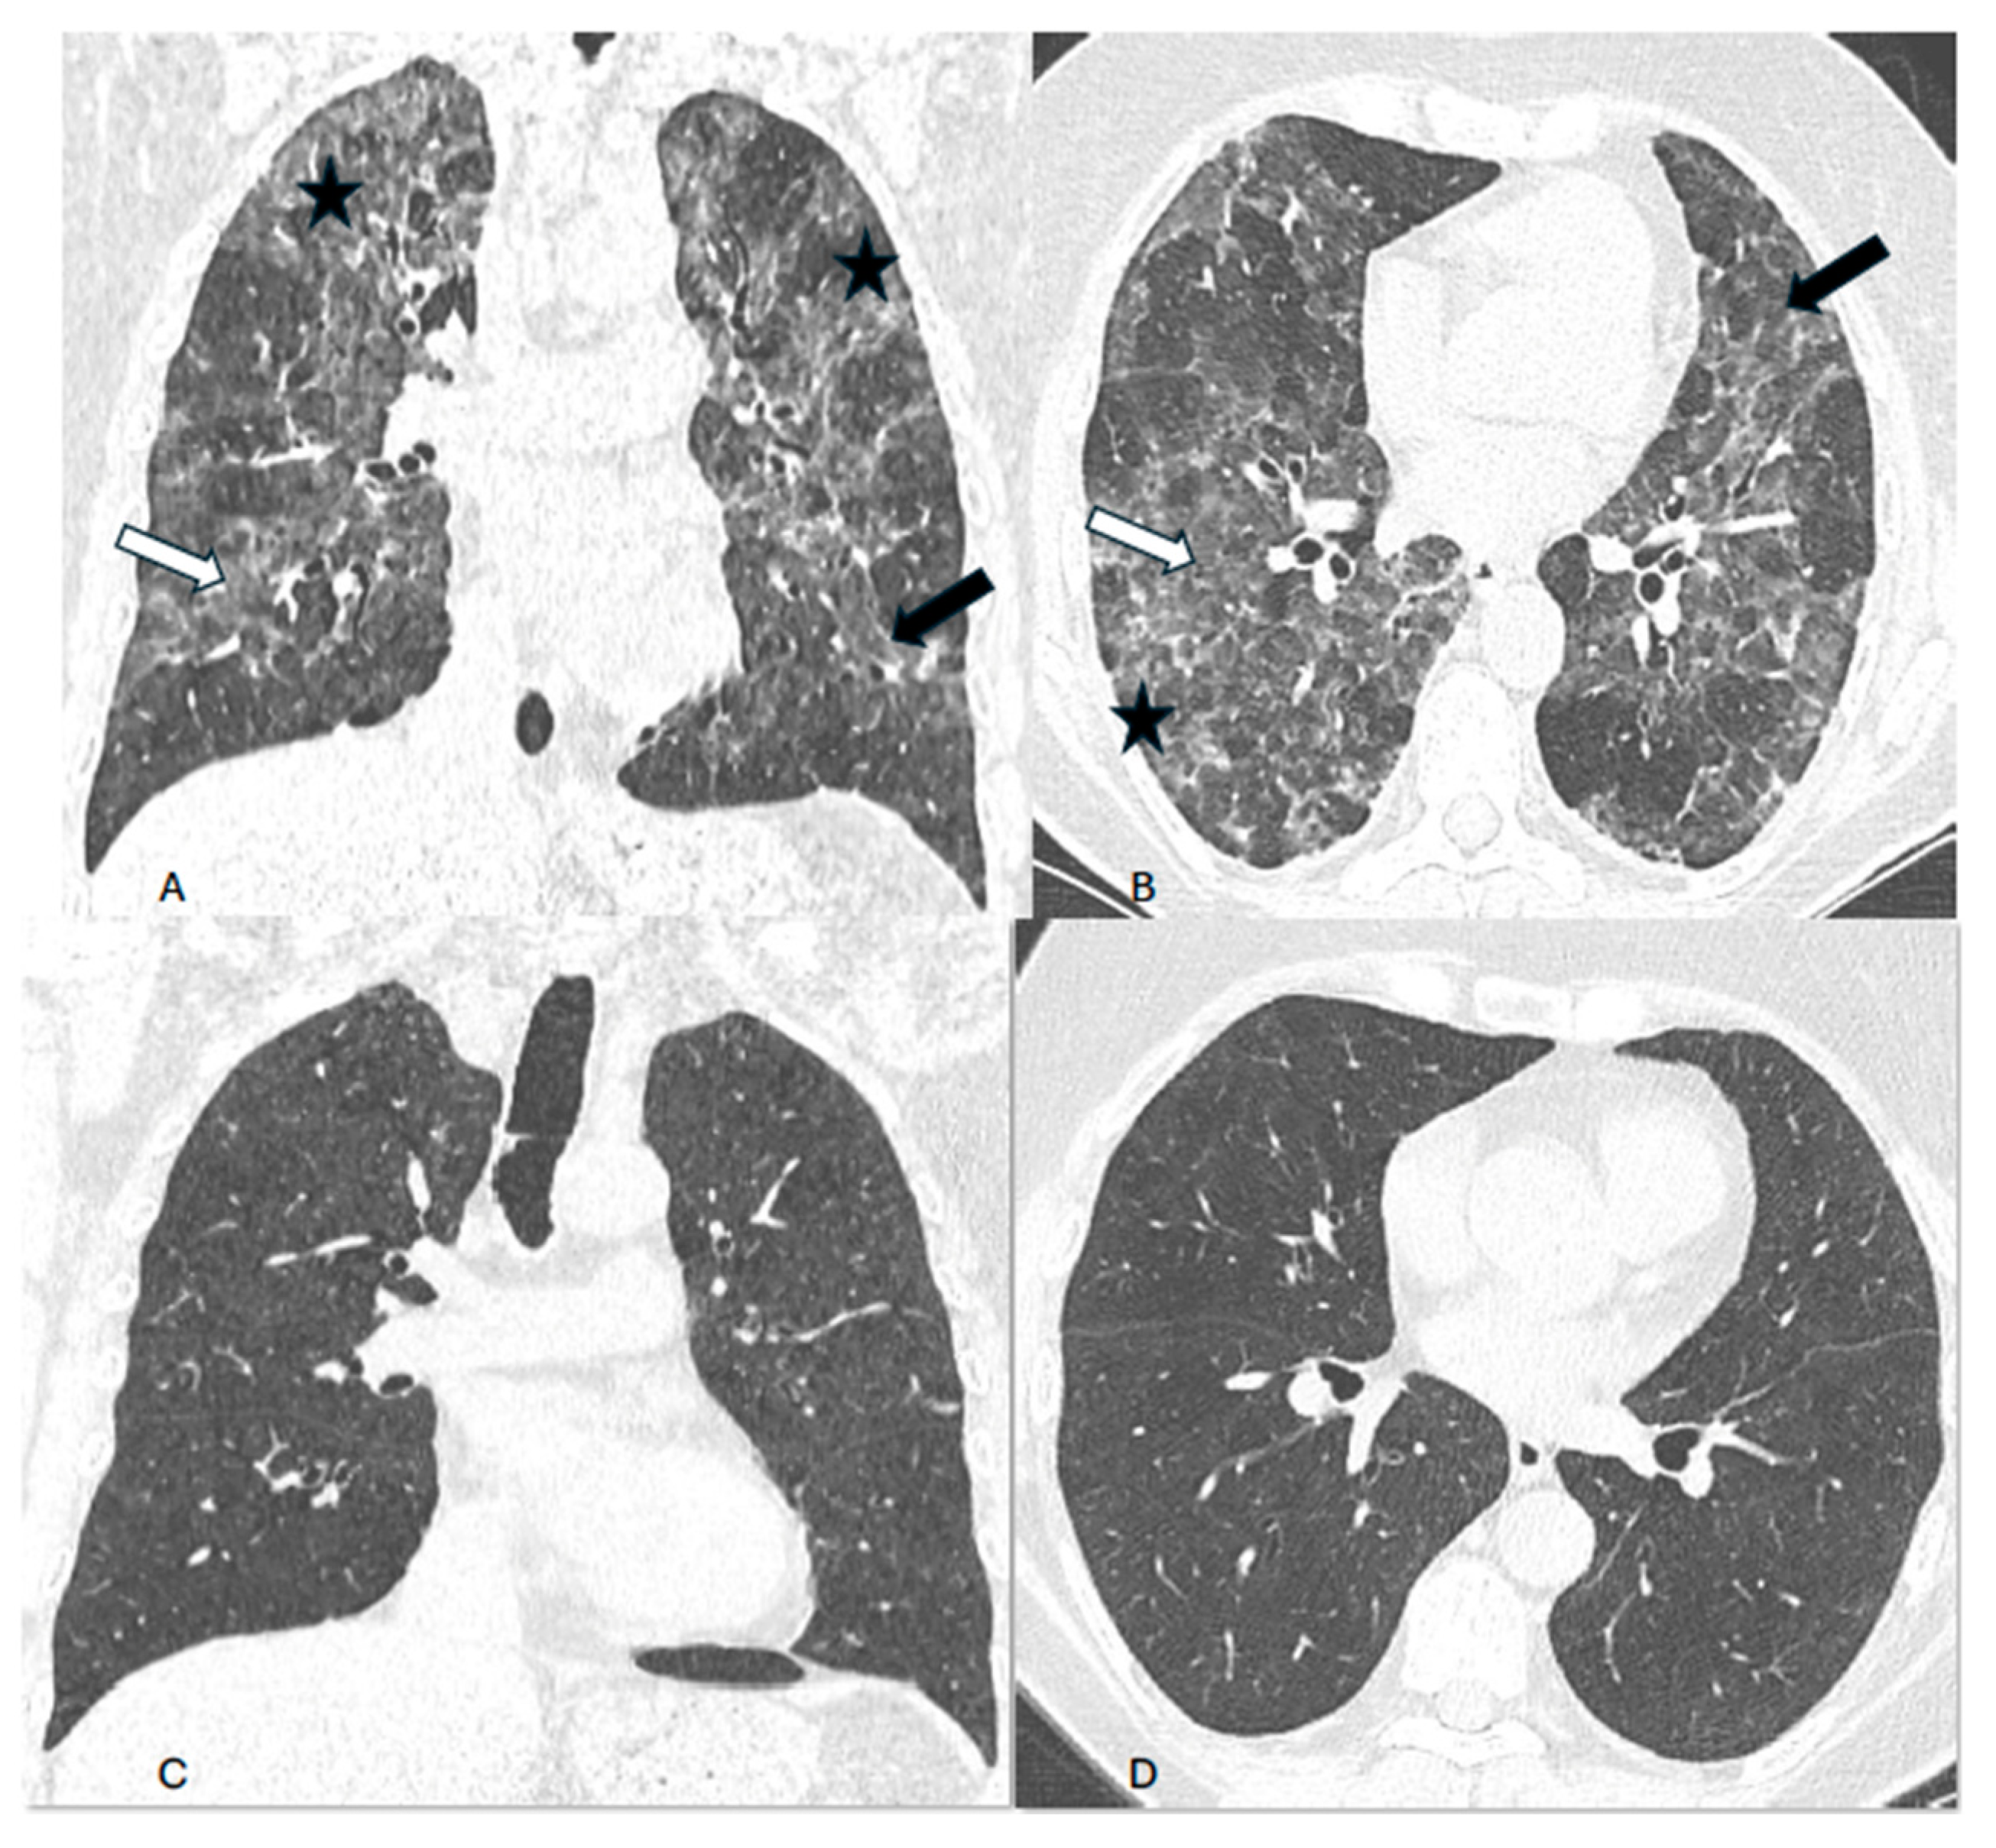

Background. Hypersensitivity pneumonitis (HP) is an increasingly recognized interstitial lung disease, developing as a result of exposition to inhaled, mostly organic, antigens. Two types of the disease are presently distinguished based on HRCT pattern and/or lung biopsy: fibrotic and non-fibrotic (non-fHP). Complete antigen avoidance is the principle of non-fHP treatment. The indications for steroids use in non-fHP depend on the clinical course of the disease. Case presentations. We present three patients in whom acute respiratory failure was diagnosed as the first sign of non-fHP. Intravenous prednisolone, followed by oral therapy with prednisone in diminishing doses, resulted in marked clinical improvement. Respiratory failure subsided within a few days, but regression of lung opacities lasted from 3 to 7 months. In one patient, the discrete reticular opacities, suggestive of the early phase of lung fibrosis, were present on HRCT, but complete regression of lung disease was achieved in the course of treatment. The patients were instructed to avoid antigens exposure; nevertheless, in one of them, a relapse of the disease, requiring a temporal increase of prednisone dose, was observed. Conclusions. Non-fHP may present as sudden-onset hypoxemic respiratory failure. In such patients, the diagnosis is based on medical history concerning the exposition to inciting antigens and characteristic HRCT pattern. Intravenous therapy with prednisolone results in quick resolution of respiratory failure, and BAL performed with a few days of delay may still be of diagnostic value. Ground glass opacities and air trapping may persist for months from exposure.